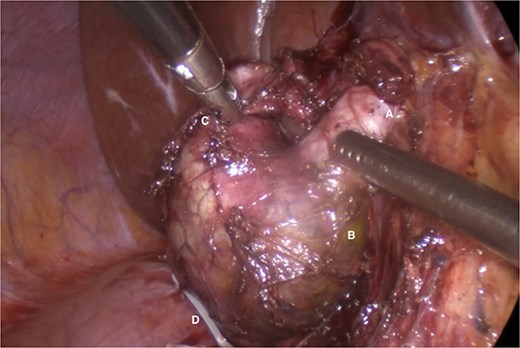

Given the imaging findings and previous AP, laparoscopic surgical management was indicated. Intraoperatively, a fusiform Type IC CC and a Type VI CDC were confirmed (Fig. 2). Complete laparoscopic excision of both cysts was performed, followed by biliodigestive reconstruction (Fig. 3).

Common hepatic duct (A), fusiform dilatation of the common bile duct (B), cystic duct cyst (C), polymeric clip on the distal portion of the common bile duct once the distal dissection and resection at this level has been completed (D).